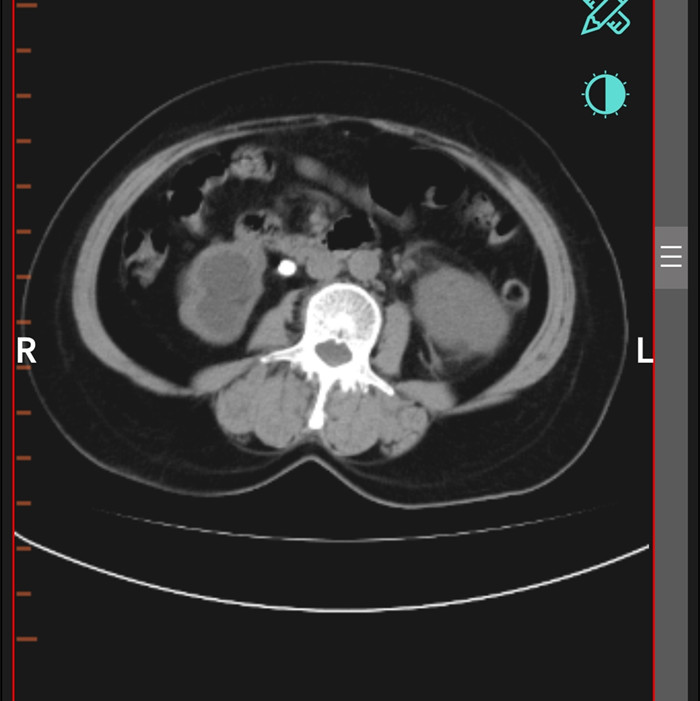

柴女士,62歲,北川縣擂鼓鎮(zhèn)人,因腰右側(cè)疼痛難忍,她來到北川羌族自治縣人民醫(yī)院就診,經(jīng)檢查提示,柴女士右輸尿管上段結(jié)石嵌頓引起重度腎積水。

“要及時解除梗阻,可以行腹腔鏡輸尿管切開取石術(shù)取代開放手術(shù)?!痹谥靹τ碌膸ьI(lǐng)下,這支剛剛成立的“泌尿外科團隊”,僅用了一個半小時就完成了手術(shù)?!案骨荤R輸尿管切開取石術(shù)創(chuàng)傷小,患者腰腹部只有3個戳孔,術(shù)后恢復快?!敝靹τ抡f。